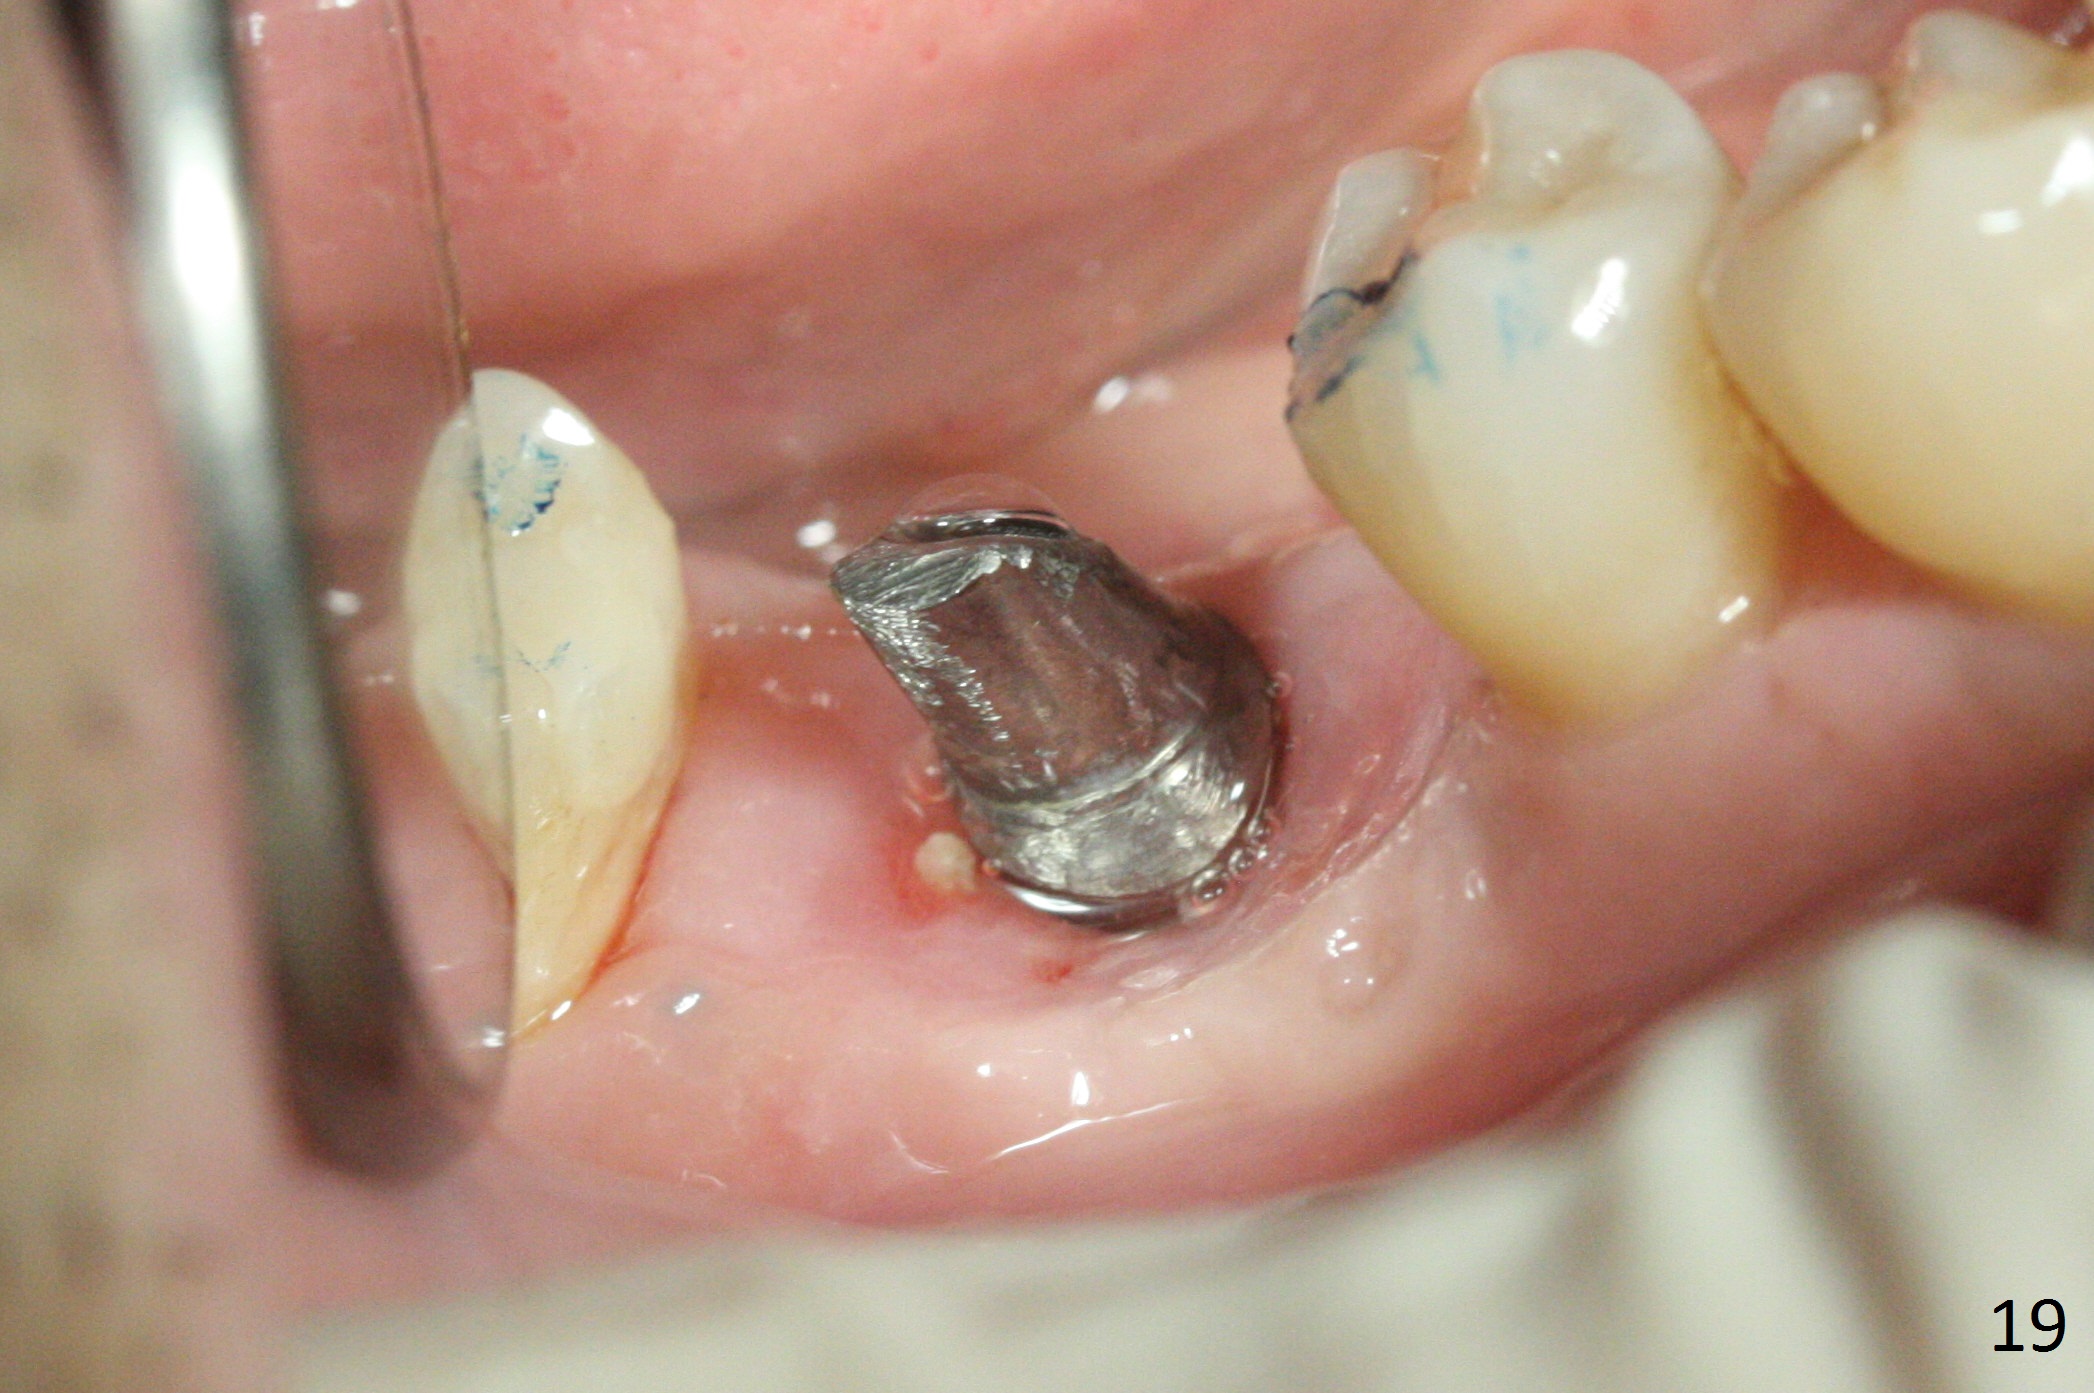

Three weeks later (5.5 months postop), a permanent crown tries in with healthy keratinized gingiva (Fig.18). The provisional keeps normal gingival bed (Fig.19), while the abutment forms tissue cuff (Fig.20). After cementation, PA shows bone regeneration (Fig.21). The gingiva remains healthy 8.5 months post cementation (Fig.22). Bone density around the implant increases 1 year 2 months post cementation (Fig.24). The gingiva remains healthy 2 years 4 months post cementation (Fig.25).